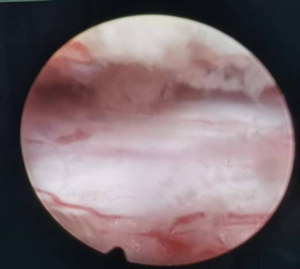

患者为70岁女性,因“双下肢麻木、乏力,行走困难1年余”入院。磁共振(MRI)检查显示T10/11单节段椎管严重狭窄,脊髓明显受压。患者症状进行性加重,保守治疗无效,但因高龄且合并高血压,对传统开放手术心存顾虑。我院疼痛科团队与安医大一附院疼痛科专家团队对患者病情进行深入的讨论,详细分析了患者的影像学资料,制订周密的手术方案,决定行局麻内镜下胸椎间管减压术。手术当日,在张荣宜主任全程指导下,我院疼痛科医疗团队精准操作,通过一个约7毫米的切口,在内镜清晰视野下,成功解除神经压迫,术后可见硬膜囊搏动恢复良好。患者术中生命体征平稳,安返病房。次日,患者即感觉下肢麻木症状减轻,并可在家属辅助下早期下床活动。术后1月,患者双下肢麻木、乏力显著缓解,可独立下床行走,步态明显改善。该技术的成功应用,为本地因高龄、基础疾病多等因素无法耐受或不愿接受开放手术的胸椎管狭窄患者,提供了一个更安全、高效、创伤小的治疗新选择。(供稿:沈凡)